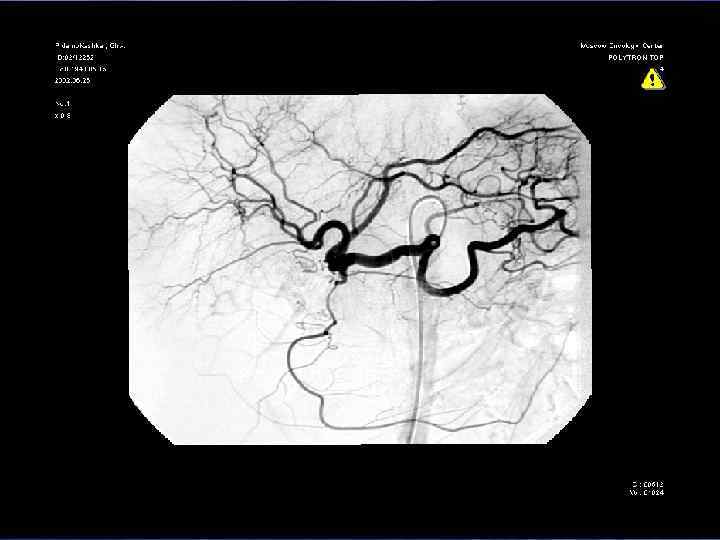

Классификация вовлечения магистральных сосудов по Nakao et al в зависимости ангиографической картины и сравнение с данными послеоперационного гистологического исследования Ангиографические типы Гистологическое подтверждение вовлечения сосудов (%) Тип А – не измененная ангиограмма 0 Тип В – одностороннее сужение 20 Тип С – двухстороннее сужение 70 Тип D – стеноз, обструкция с наличием коллатеральных вен 92

Верхняя мезентерикография после резекции чревного ствола с ушиванием обоих концов сосуда наглухо. Кровоснабжение печени осуществляется через гастродуоденальную артерию